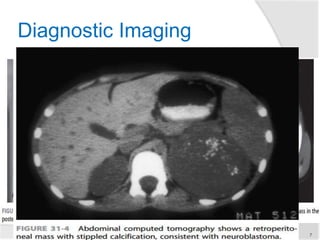

Diagnostic Imaging

 CT scan

 Calcification in ~ 85% of tumors,

and intraspinal extension of the

tumor on contrast-enhanced CT

 Overall, contrast-enhanced CT

has 82% accuracy in defining

neuroblastoma extent, with the

accuracy increasing to nearly

97% when performed with a

bone scan

►Imaging findings

 Stippled calcification or

LN with calcification

 Displace the kidney

inferiorly

 Crossing the midline

 Encasing/displace vessels

 Paravertebral mass—

spinal extension